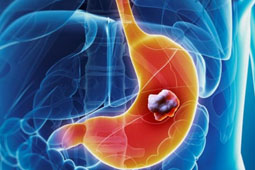

Πεπτικό έλκος είναι η διάβρωση του επιθηλίου του βλεννογόνου του στομάχου ή του δωδεκαδακτύλου, η οποία μπορεί να επεκταθεί μέχρι και τη μυϊκή στοιβάδα. Πεπτικό έλκος είναι η διάβρωση του επιθηλίου του βλεννογόνου του στομάχου ή του δωδεκαδακτύλου, η οποία μπορεί να επεκταθεί μέχρι και τη μυϊκή στοιβάδα. |